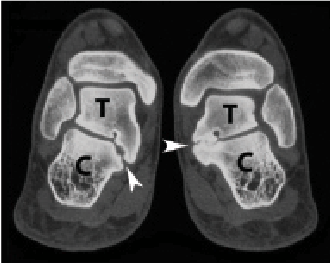

The second criterion for consideration is the articular involvement of the coalition. The 2 most common tarsal coalitions are the talocalcaneal coalition and the calcaneonavicular coalition. The talocalcaneal coalition, along with other tarsal coalitions such as talonavicular, calcaneocuboid, etc., are present within otherwise normal joints and can be deemed “intraarticular coalitions” or coalitions occurring within a joint space. Conversely, the calcaneonavicular coalition, along with other coalitions such as a cubonavicular coalition, can be considered “extraarticular coalitions” as they occur outside a normal joint space. Reasonably then, with other factors being equal, one would expect a resection surgical approach to be more successful for an “extraarticular coalition” than an “intraarticular coalition,” as one is not destroying a portion of a normal joint when removing the “extraarticular coalition.”

When I authored my paper in 1991 regarding these surgical criteria, I coined the term “Articular Classification System” to describe their combined use in deciding whether to perform surgical resection of a tarsal coalition or surgical arthrodesis of the involved joints (Figure 2).1 I believe this classification system for tarsal coalitions is more helpful in deciding the best surgical approach than prior described classifications. Since the publication of the “Articular Classification System” manuscript, several additional conditions have been documented in the literature as possible important criteria to be considered in the surgical decision-making process.2 These criteria are primarily important for talocalcaneal coalitions and are less important for calcaneonavicular coalitions. These criteria include the size of the tarsal coalition, the morphologic shape of the tarsal coalition, and the degree of heel valgus that is present. Arbitrarily, many surgeons have argued that surgical resection of any “intraarticular coalition” is less likely to be successful if more than 50% of the joint is involved.2 It makes sense that joints more extensively damaged and/or mechanically distorted by the presence of a tarsal coalition would be less likely to have success with resection, as there is less joint remaining after the resection.